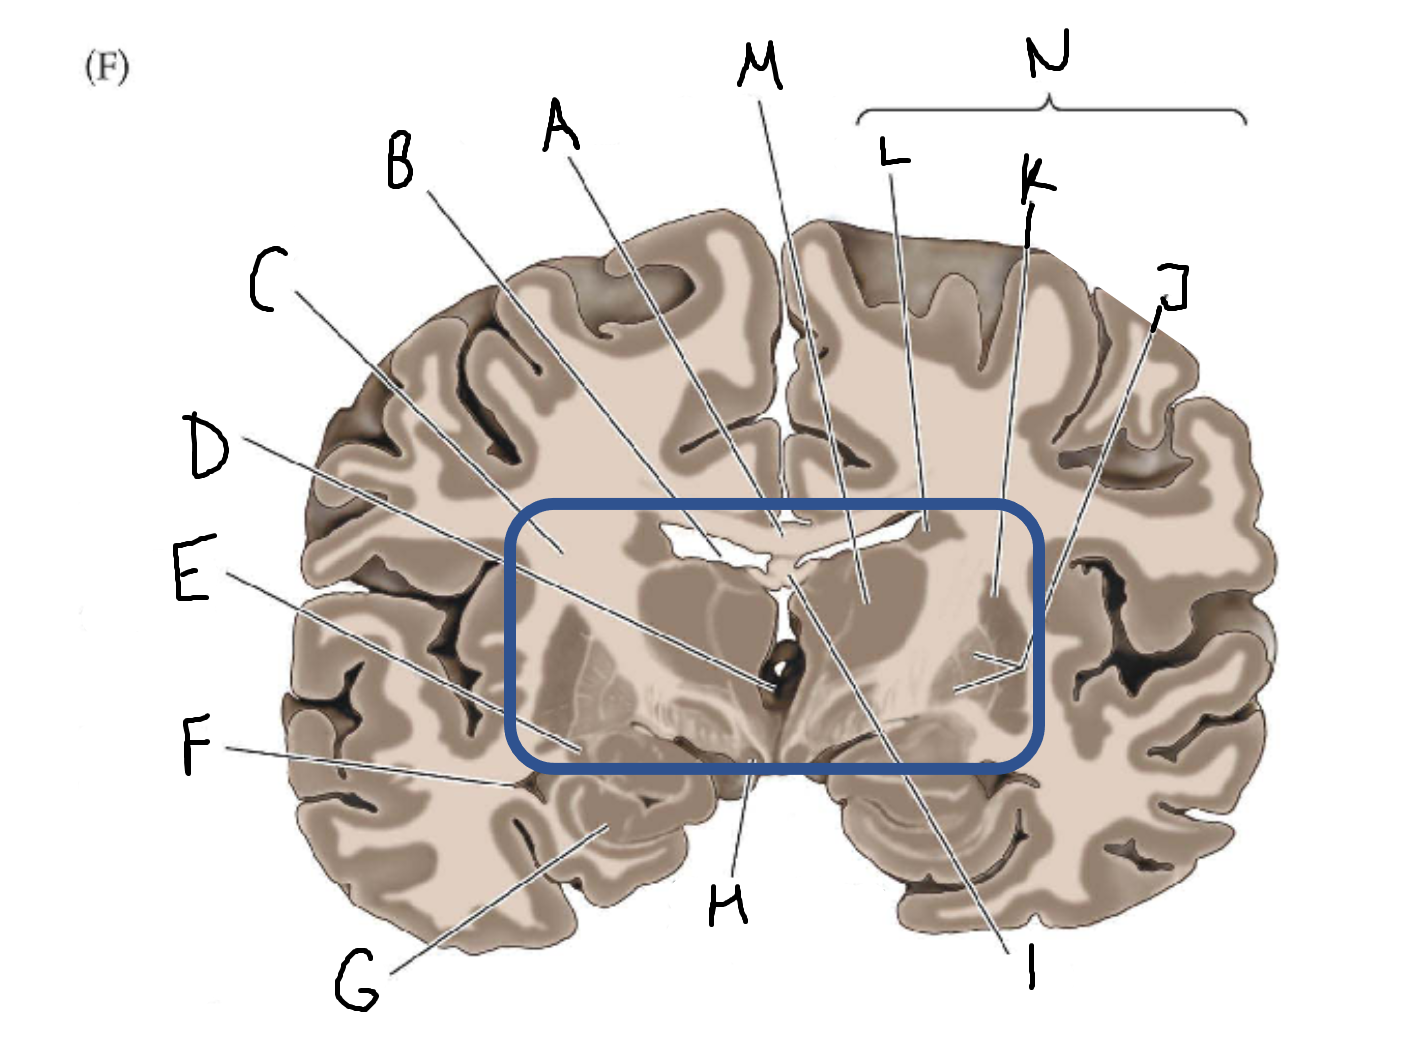

A

corpus callosum

B

lateral ventricle

C

internal capsule

D

third ventricle

E

tail of caudate nucleus

F

lateral ventricle

G

hippocampus

H

mammillary body

I

fornix

J

globus pallidus

K

putamen

L

caudate

M

thalamus

N

basal ganglia